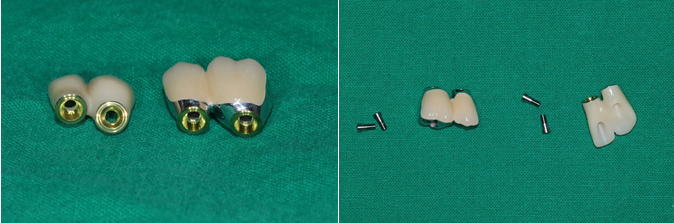

전치부는 지르코니아, 구치부는 보험임플란트 pfm 으로 제작 (70세 여자)

c.c: 앞니가 부러졌고, 오른쪽 어금니가 아파요.